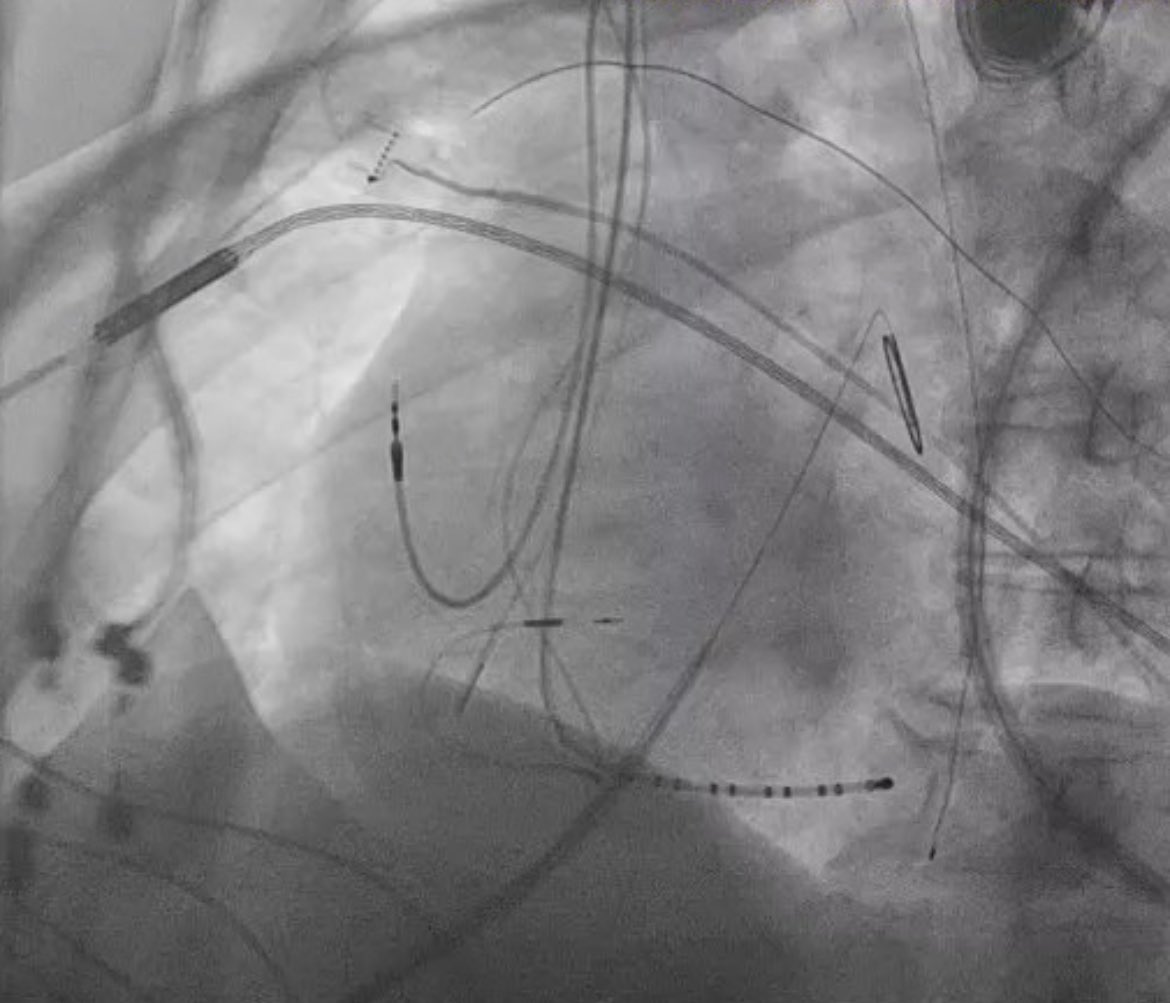

Michael Gurin Heart Rhythm Society Very excited to share the work presented by Adrian Petzl, simultaneously published in @JACCjournals. He describes a PAC ablation limited by infrequent intraprocedural PACs. With direct, intravascular electrical sympathetic stimulation, PACs were induced and ablation facilitated.

Intracardiac echocardiography inside left atrium detects wall-adherent thrombus before ablation and prevents potential major thromboembolic complication Adrian Petzl Fermin Carlos Garcia heartrhythmjournal.com/article/S1547-…

Intracardiac echocardiography inside left atrium detects wall-adherent thrombus before ablation and prevents potential major thromboembolic complication